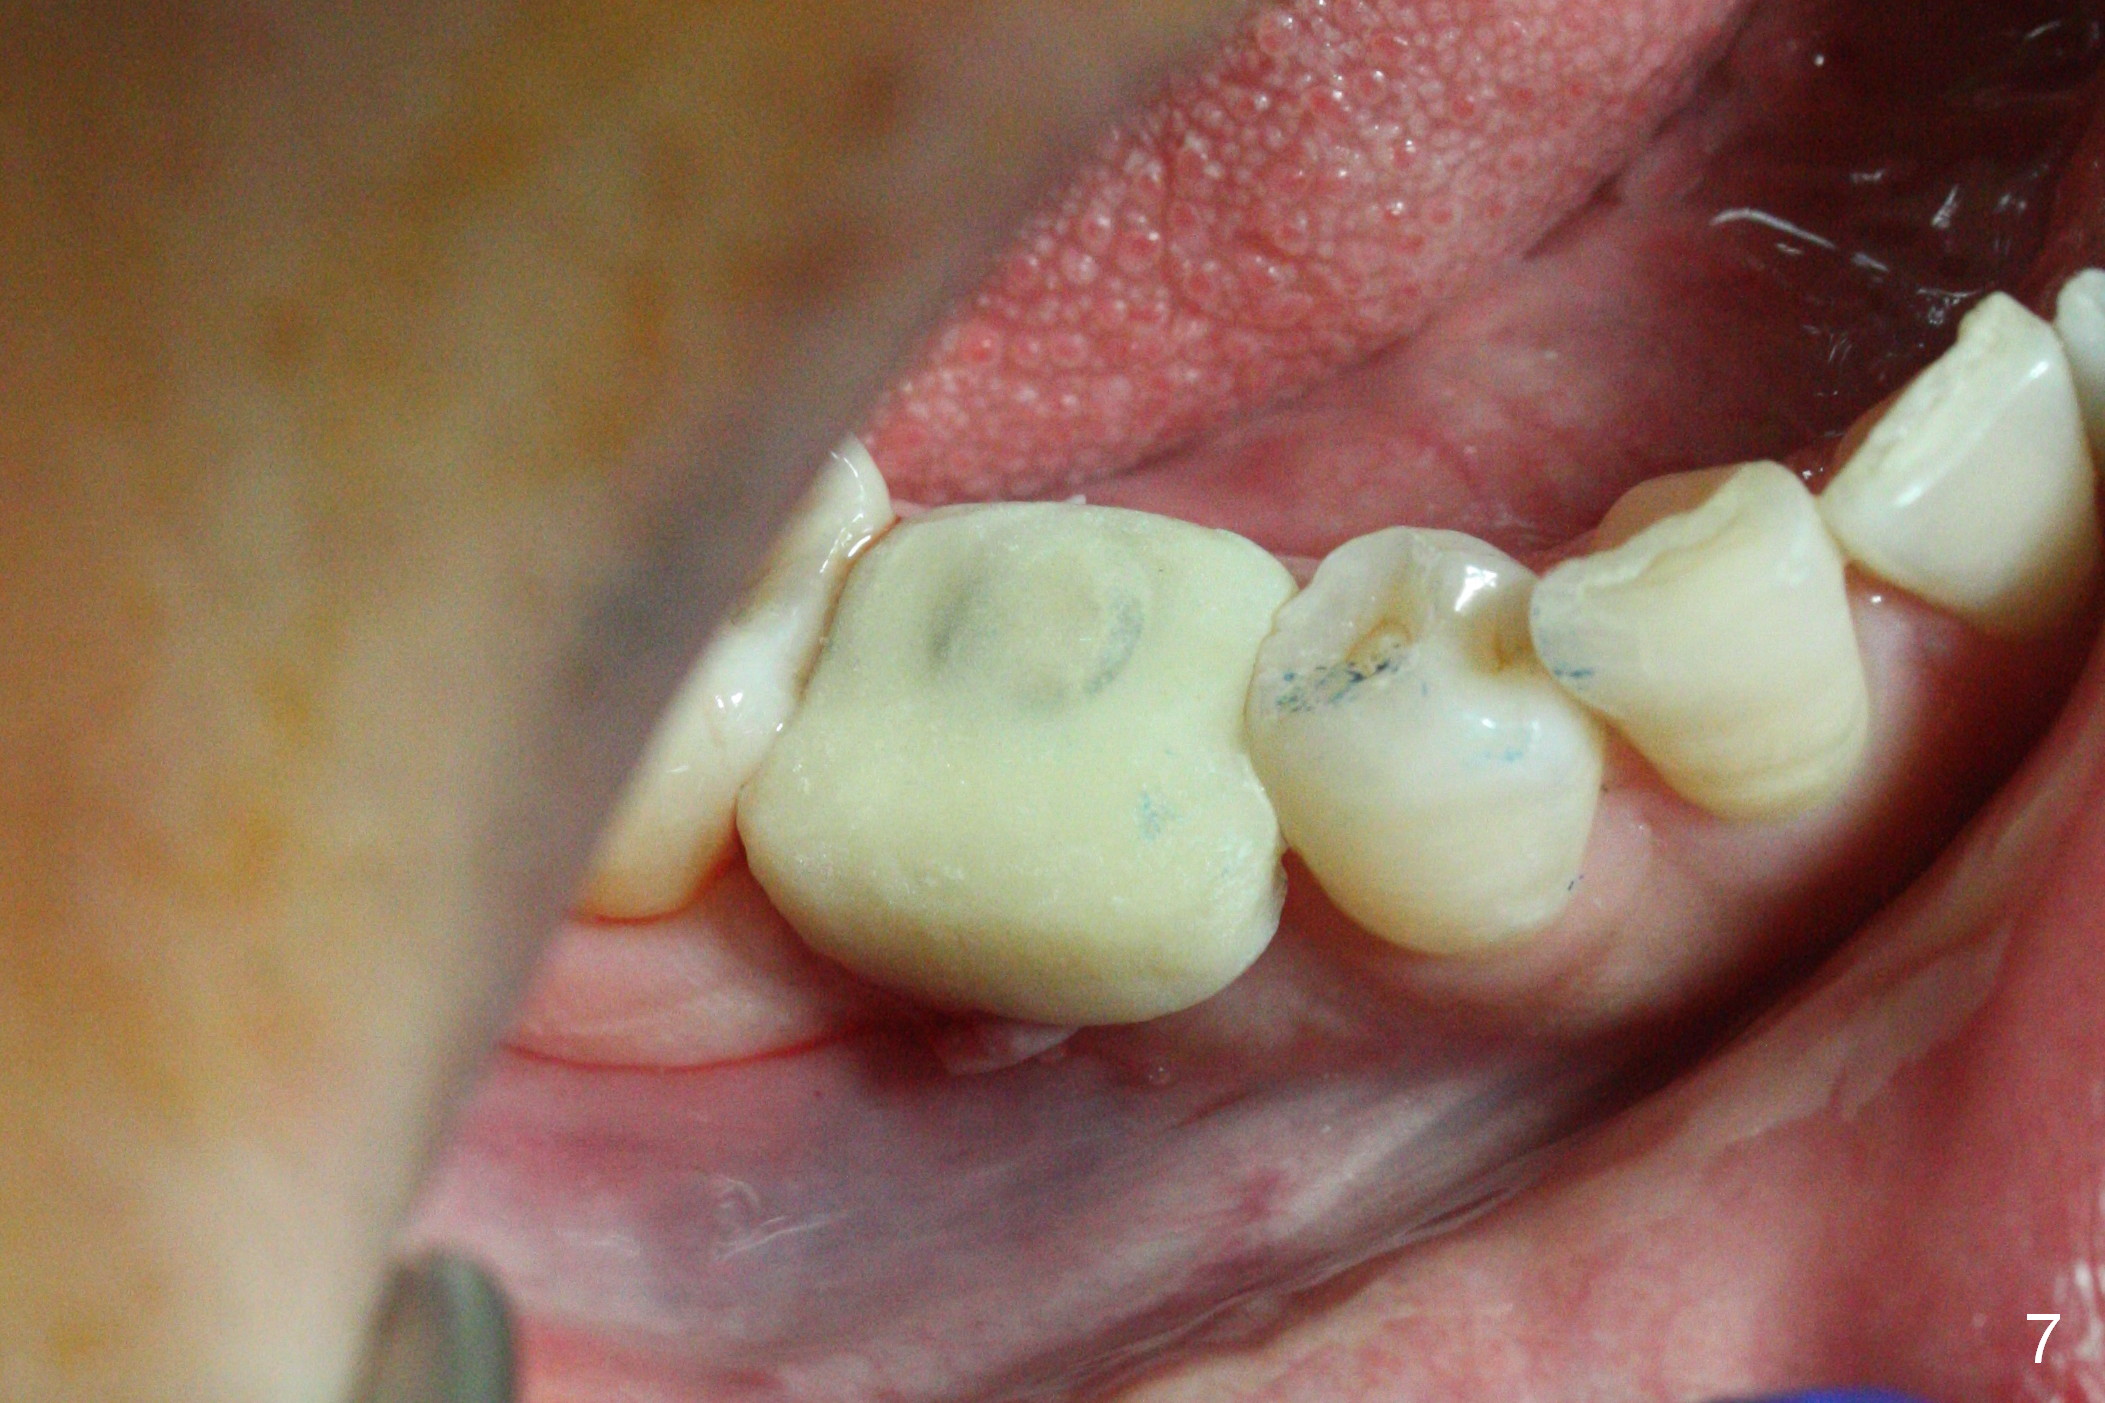

The lower 2nd primary molar has buccal furca lesion (Fig.1 *) with the thin buccal plate (Fig.2). Osteotomy is initiated in the sloped septum (Fig.3). After use of Magic Drill (MD) 3.3 mm for 13 mm and MD 3.8 mm for 11 mm, placement of a 4x11 mm IBS implant meets resistance because of the dense bone (Fig.4-6, red dashed line: Mental Loop) with final insertion torque >50 Ncm. After placement of a 6x4(3) mm abutment and autogenous bone in the remaining shallow sockets (Fig.6), a provisional is fabricated (Fig.7). Finally periodontal dressing is applied. Impression is taken 3 months postop (Fig.8). Buccal infection develops 2 weeks post cementation (Fig.9). When the crown/abutment is removed, there is no residual cement. The implant threads can be felt through the fistula. After soft tissue debridement and copious irrigation, Arestin is placed in the fistula. The latter disappears 15 days post debridement. The patient feels better and moves out of state. It appears that early periimplantitis develops because of the preexisting buccal furca lesion and failure to place the implant deep. The implant will be placed deep after loosening a little (since there is apical space (Fig.8 white line)) or removed, truncated at the apex and placed lower than the buccal crest.